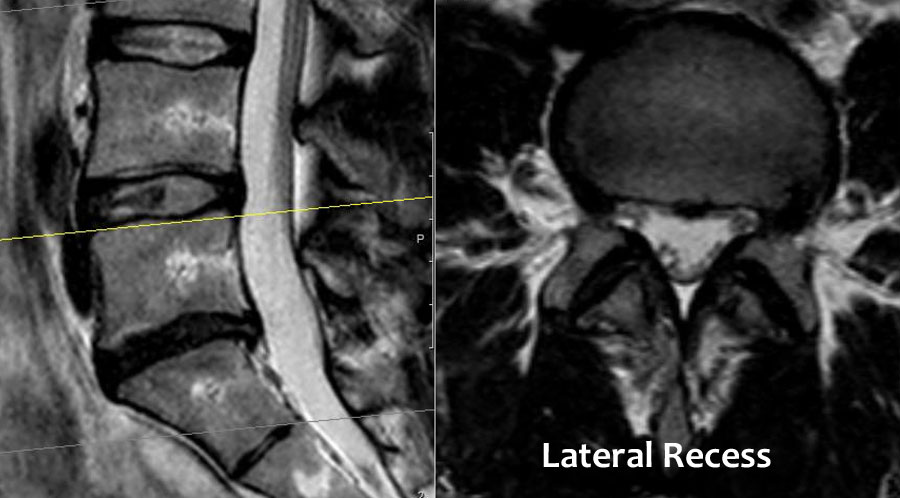

Chủ yếu do thoát vị đĩa đệm và ít thường gặp hơn do hẹp ống sống. - Mức độ ngách bên.

Đây là vùng nằm phía dưới đĩa đệm, nơi rễ thần kinh đi theo hướng bên hơn về phía lỗ liên hợp.

Hẹp ngách bên được gây ra bởi thoái hóa khớp mỏm khớp, thường kết hợp với phì đại dây chằng vàng và phồng đĩa đệm. - Lỗ liên hợp.

Cuộn qua các hình ảnh để quan sát đường đi của các rễ thần kinh tại mức độ đĩa đệm, ngách bên, lỗ liên hợp và ngoài lỗ liên hợp.

Tại mỗi mức độ có thể thấy các bệnh lý đặc trưng, nhưng có sự chồng lấp đáng kể.

Ở bệnh nhân thoái hóa khớp mỏm khớp, các gai xương có thể phát triển vào trong và làm hẹp ngách bên, hoặc phát triển lên trên và làm hẹp lỗ liên hợp.

Khi thoái hóa khớp mỏm khớp nặng xảy ra hai bên, có thể gây hẹp ống sống và chèn ép tất cả các rễ thần kinh tại tầng đó.